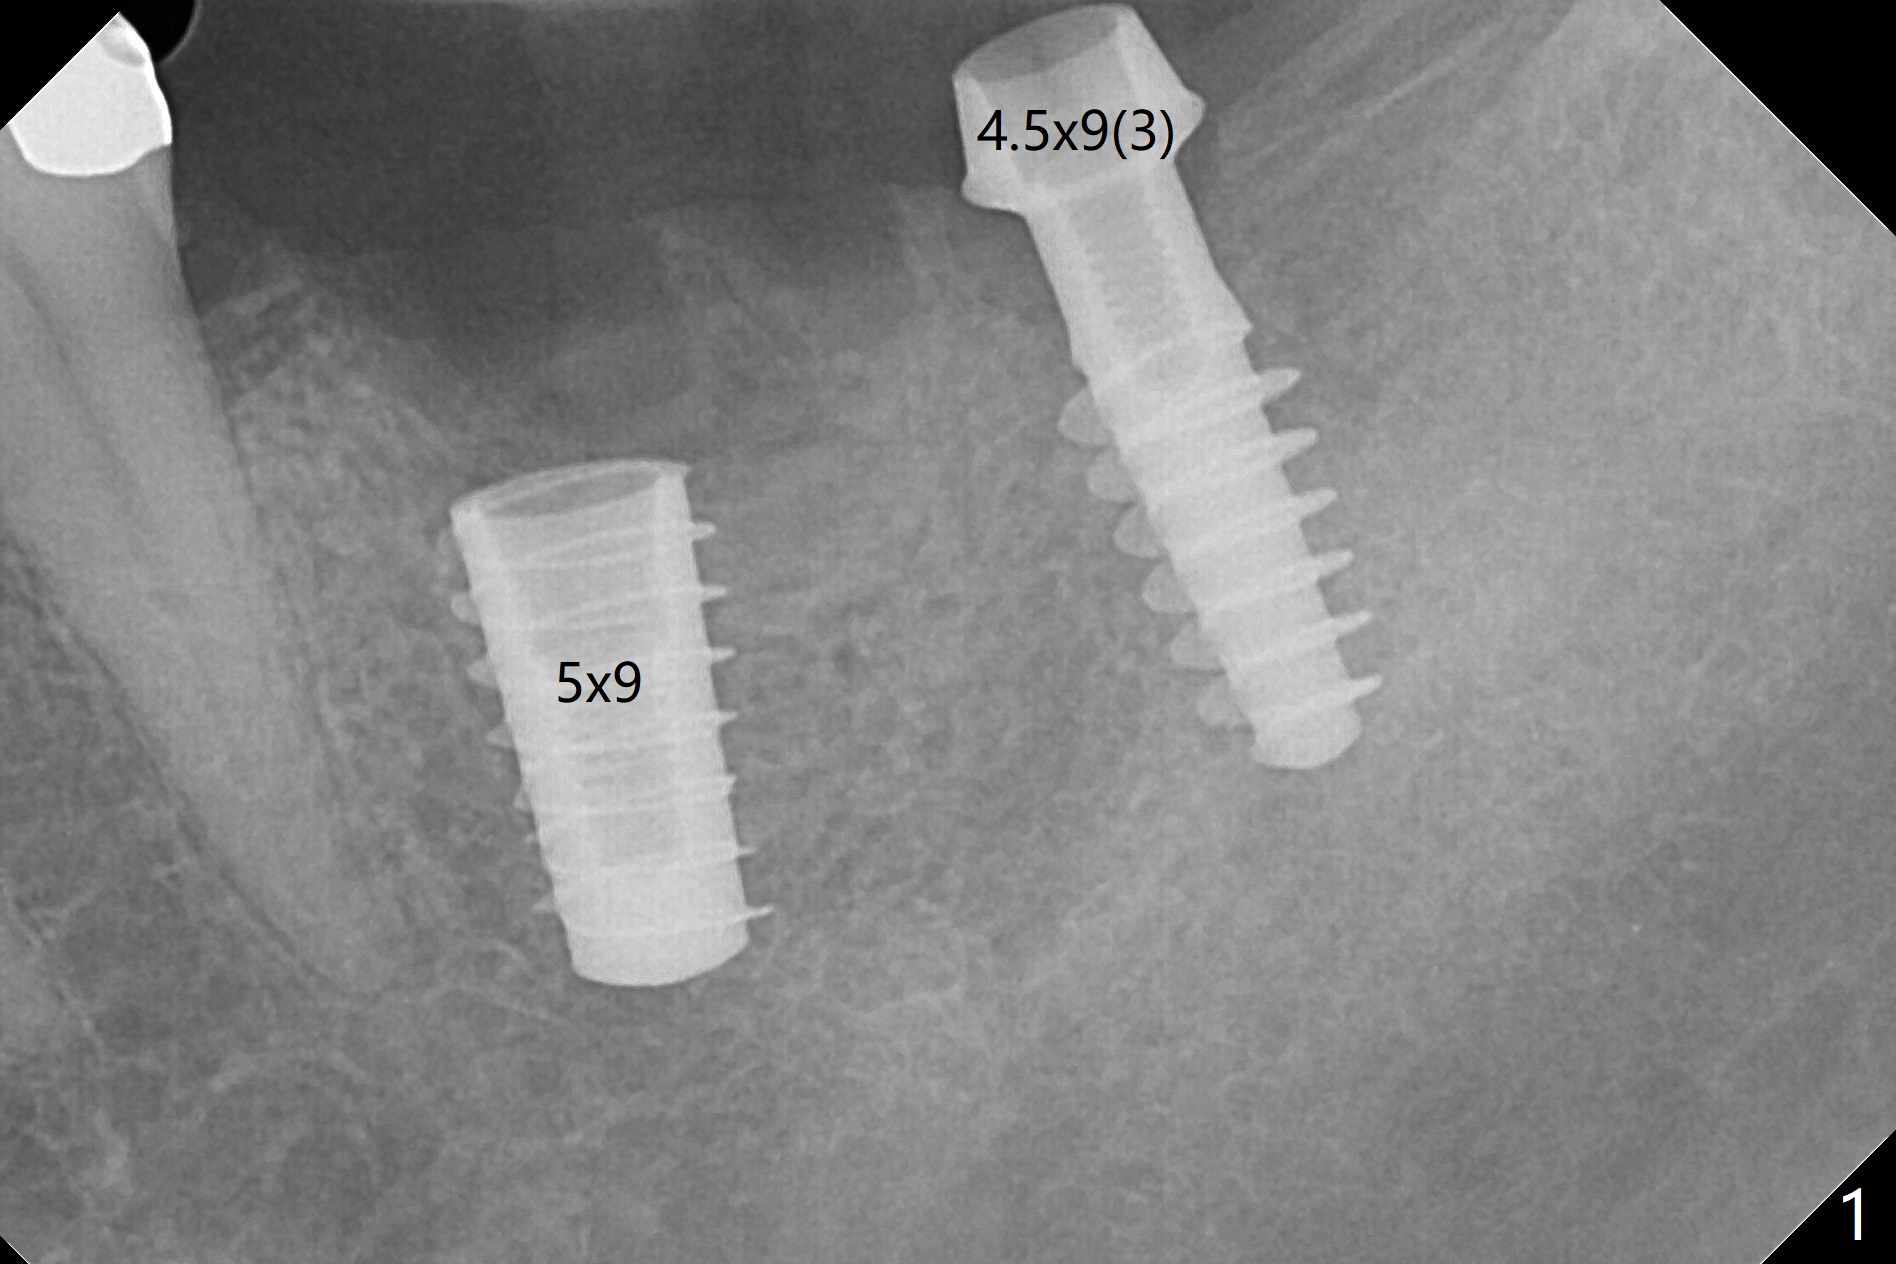

After osteotomy according to drill sequence except no tap at #18, a 5x9 mm FC at #19 achieves insertion torque at 20 Ncm, while a.4.5x9(3) mm Magicore <10 Ncm (Fig.1,2), probably due to the fact the core (middle portion) of Magicore is small, dictating underprep (in diameter) when the bone is not hard. In addition, IS implant driver cannot be engaged to Magicore so that the placement of the latter is free hand. Because of supraeruption of the opposing teeth, the abutment at #19 is heavily reduced, whereas the Magicore is placed super low (Fig.2). The latter may be backed up or crown lengthening is necessary. In fact neither is necessary, since there is crestal bone loss at #18 nearly 3 months postop (Fig.3 *). There is no difficulty in placing 4.5 mm healing cuff.